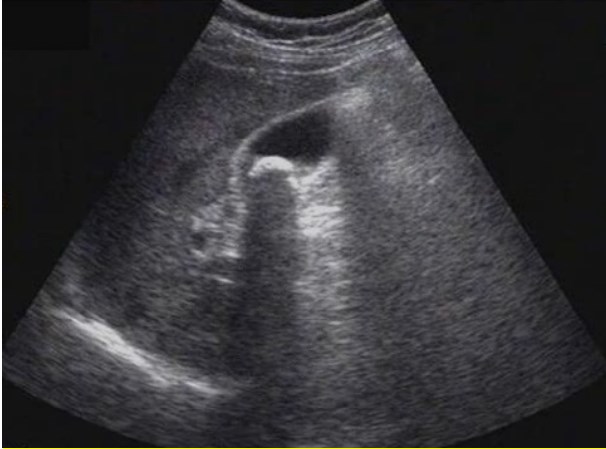

试题:患者女性,50岁,间断上腹隐痛半年,诊断为(2分)

A.肝癌

B.肝硬化

C.胆囊结石

D.肾结石

【答案】C